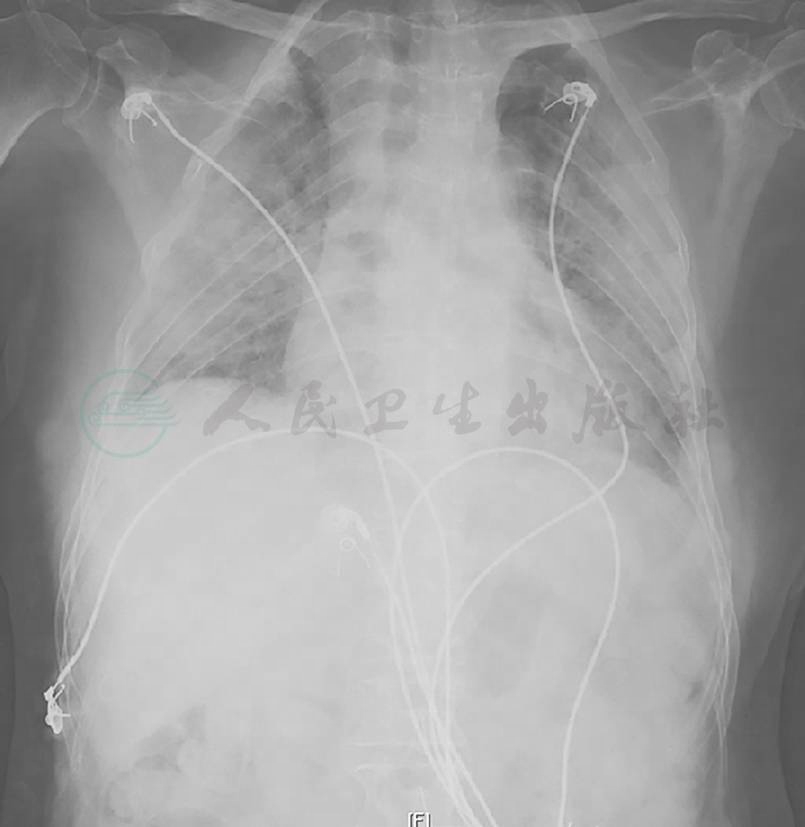

胸部X线检查可见双肺弥漫高密度影,双侧少量胸腔积液(图4),1个月后病灶进一步增多、加重(图5)。胸部CT显示病灶进一步融合增多,伴双侧胸腔积液和心包积液(图6)。

图4 胸部X线表现(2015-05-23)

胸部X线片可见双肺多发斑片影,双侧肋膈角显示不清,变钝

图5 胸部X线表现(2015-06-23)

胸部X线片可见双肺多发斑片影较前略加重,双肋膈角变钝